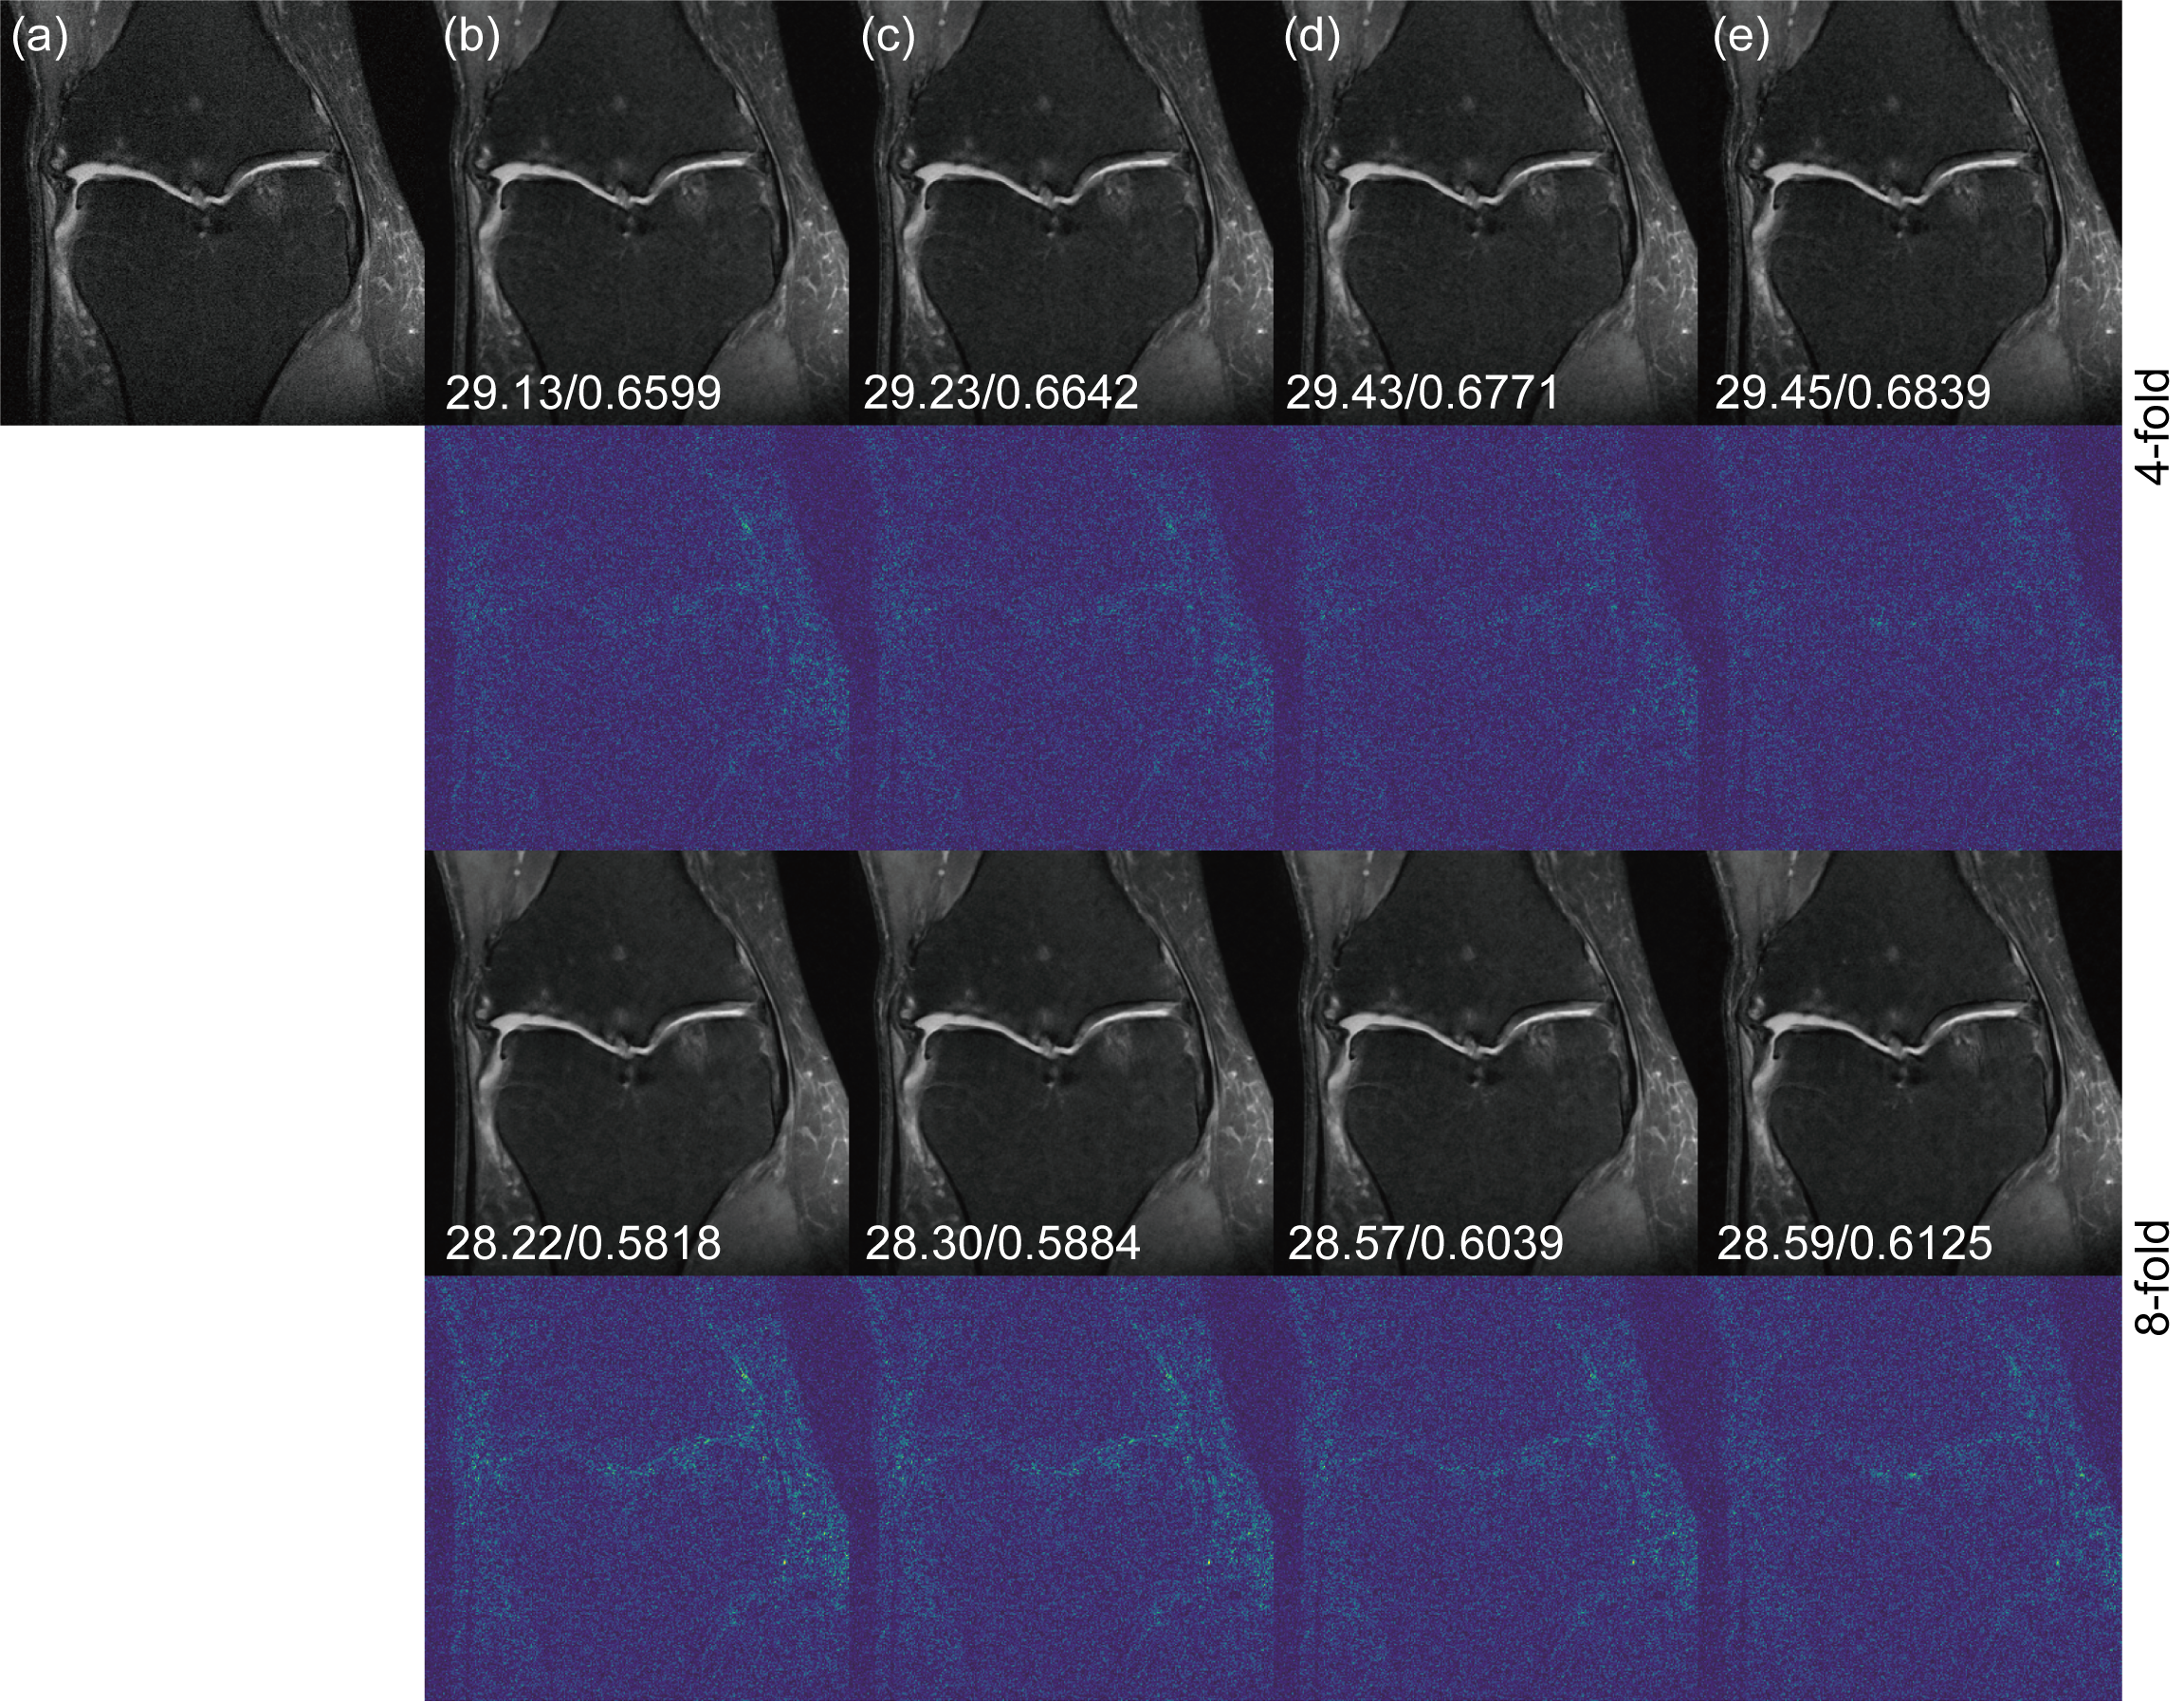

Fig. 3 demonstrates reconstruction results for 4-fold and 8-fold Cartesian under-sampling masks. We compare our k-space cold diffusion model with U-Net, W-Net and E2E-VarNet. Corresponding error maps are shown under each reconstruction image. All error maps have been magnified five times for better demonstration. We find that our k-space cold diffusion model preserves more image details and leads to cleaner error maps compared to other models. Tab. 1 provides evaluation metrics for the 4-fold and 8-fold Cartesian under-sampling reconstructions, showing that our model outperforms others with a PSNR/SSIM of 30.58/0.7150 for 4-fold and 29.51/0.6414 for 8-fold. In Fig. 4 and Tab. 2, we demonstrate reconstruction results and evaluation metrics for Gaussian sampling masks with 4-fold and 8-fold acceleration tasks. Our method outperforms others with a PSNR/SSIM of 30.31/0.7059 and 29.59/0.6416 for 4-fold and 8-fold, respectively. Similar to the Cartesian sampling reconstruction tasks, we found our model preserves more image details and textures and gives out cleaner error maps.